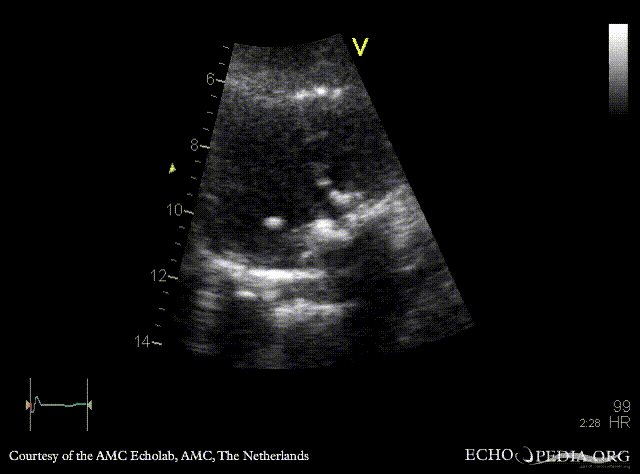

Case 108